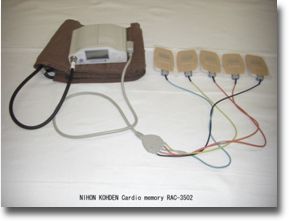

ホルター心電図

日常生活中の心電図を24時間(一日)にわたって記録・再生し、観察する検査法です。したがって検査翌日に再び来院していただきます。普段の行動の中で心電図がどのように変化するか、何らかの症状(動機・めまい・胸痛など)がある時の心電図が症状のない時の心電図に比べてどのように違うか、などについて調べます。検査方法は電極を胸の上に数箇所貼り付け、記録するための機械を腰にベルトで固定し、その間を細いコードで接続します。また、検査中は入浴・シャワー等はできません。

血圧ホルター心電図

ホルター心電図の機能と、24時間(一日)にわたって血圧も自動測定し、記録する2つの機能をもった検査です。昼間は30分、夜は1時間に一回血圧を測定する為、患者様には少し苦痛を与える検査です。高血圧の方などに行う検査です。